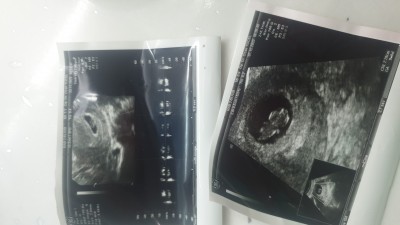

Gebelikte kese bir fasulye seklinde olup bir yuvarlak olurmu arkadaşlar bebegime 1 kiz bir erkek bir kiz diyorlar ikiz olabilirmi gebelik kesesi her ultrsyanda bi fasulye şeklinde bi.yuvarlak bilgilendirirseniz

Gebelik haftası 14

Bunlar 4 gitmemde bana verilen ultrason kagitlari

Benimkide şuan 7+3 fasulye şeklinde sonra ne olur bilemicem